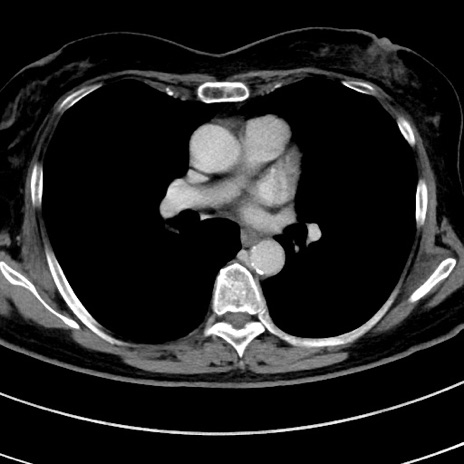

症例9(横断像)

【症例】 60歳代女性

【主訴】むかつき、みぞおちの痛み

【現病歴】3日前よりむかつきがあり、食事がとれない。

【既往歴】糖尿病

【身体所見】発熱なし、心窩部圧痛軽度あるも、腹膜刺激症状なし。

【データ】WBC 7400、CRP 1.92